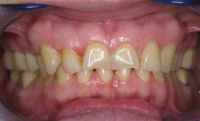

Voor de behandeling

Gebitsslijtage door een eetstoornis op jeugdige leeftijd. Door het vele spugen is er heel vaak maagzuur langs de tanden en kiezen gekomen waardoor bijna de gehele binnenzijde van de tanden is opgelost. Doordat de tanden zo dun zijn geworden, breken er gemakkelijk stukjes vanaf.